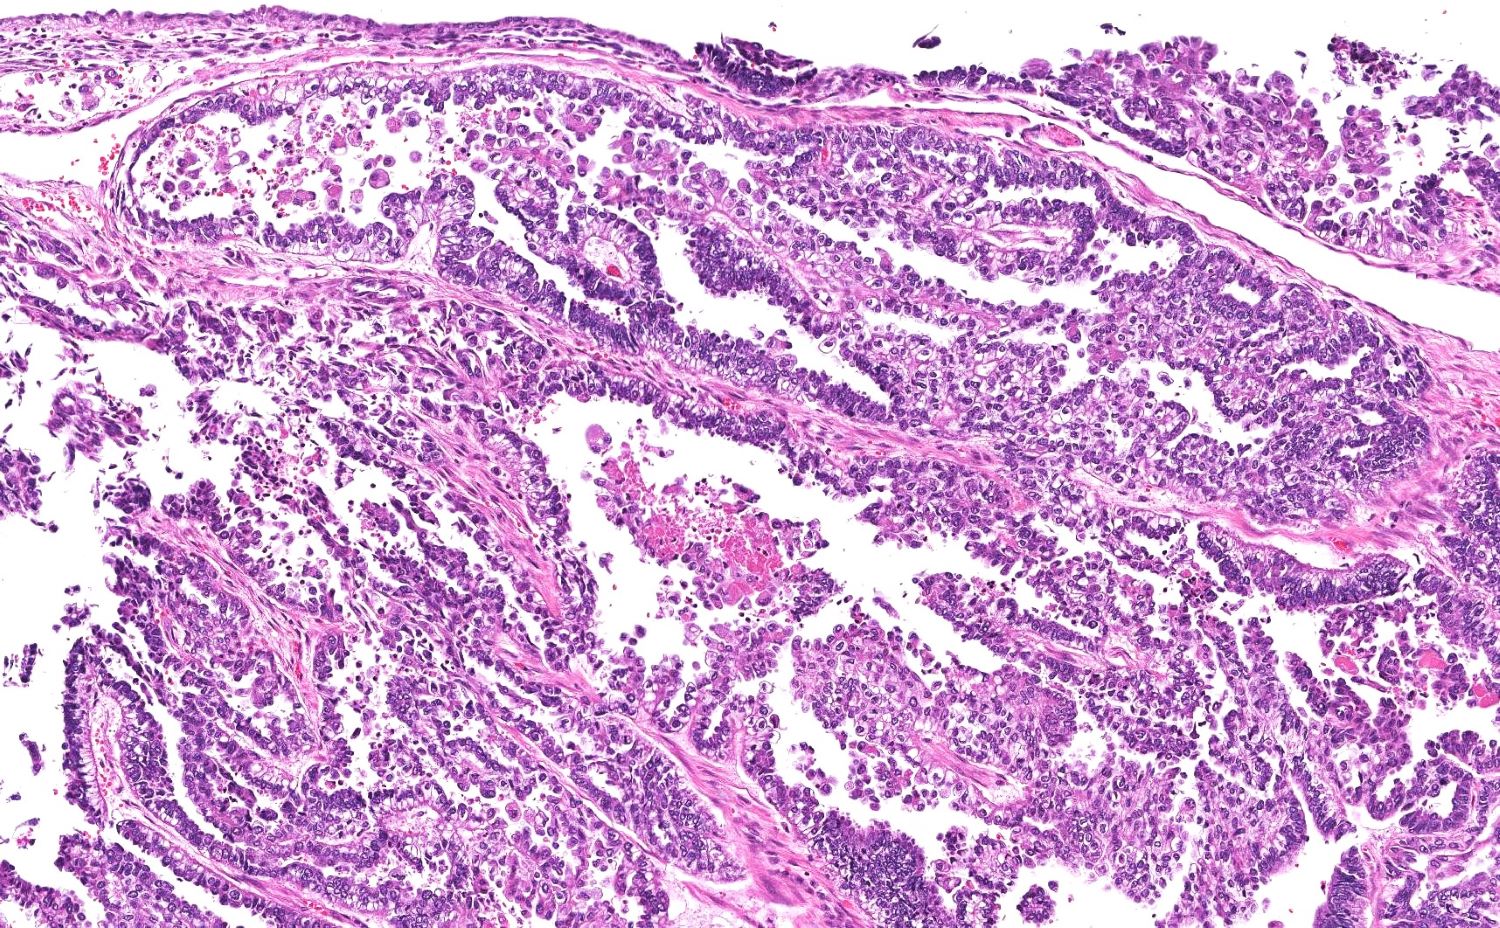

- Variety of histologic patterns that may be present within the same tumor

- Most frequently small tubules with ductal / glandular growth

- Papillary, solid growth, trabecular, retiform, sex cord-like, sieve-like, glomeruloid and spindle cell areas have all been described

- Luminal eosinophilic secretions are characteristic but not always identified

- Tumor cells can be flattened, cuboidal or columnar with mild to moderate cytological atypia

- Clear cell features can be seen but are less common

- High grade cytological atypia is usually not a predominant feature

- Nuclei show vesicular chromatin and nuclear grooves

- Sarcomatoid transformation has been seen in rare instances

- Squamous, ciliated or mucinous differentiation (metaplasia) are not present and there are no associated mesonephric remnants (J Clin Med 2021;10:698)

Microscopic (histologic) images

Contributed by Daniel Graham, M.D., Adele Wong, M.B., B.Ch., B.A.O. and Lucy Ma, M.D.